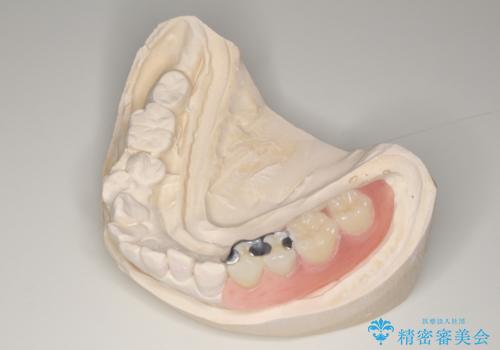

- 前歯の色が気になるとのことでご相談にいらした患者様です。診断の結果、前歯は2本とも失活していたために精密根管治療から治療を開始しました。根管治療後にウォーキングブリーチを行うことで歯の色をトーンアップさせました。患者様より周囲の歯も全体的に白くしたいとのご希望があったため、オフィスホワイトニングも併せて行いました。

- 4万円(精密根管治療・オフィスホワイトニングは除く)費用は治療当時の料金となります